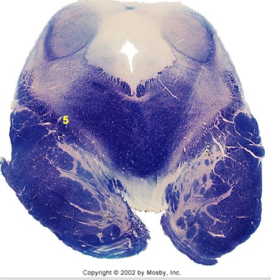

| Superior vestibular nucleus | |

| Medial lemniscus | |

| Trapezoid body | |

| Ventral trigeminothalamic tract | |

| Superior olive | |

| Longitudinal pontine fibers (corticospinal tract) | |

| Transverse pontine fibers (dark fibers) | |

| Pontine nuclei (pale) | |

| Central tegmental tract | |

| ALS | |

| Medial longitudinal fasciculus | |

| Middle cerebellar peduncle | |

| Superior cerebellar peduncle | |

| Anterior spinocerebellar tract | |

| Principle nucleus of V | |

| Mesencephalic V tract | |

| Trigeminal root fibers | |

| Motor nucleus of V | |

| Cerebellar vermis | |

| Lateral lemniscus | |

| Longitudinal pontine fibers (c-spinal, c-bulbar, c-pontine fibers) | |

| Transverse pontine fibers (dark) | |